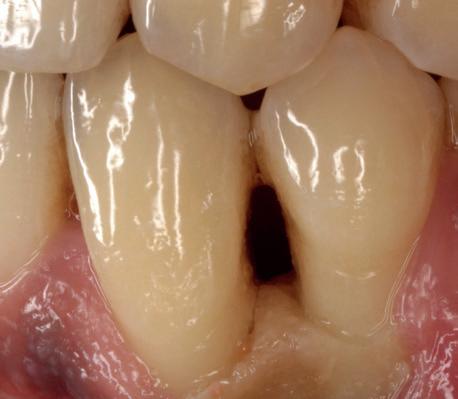

In afbeeldingen 4a-c is het resultaat drie maanden na het plaatsen van het implantaat te zien. De genezing is volledig en de verwijzer kan de suprastructuur vervaardigen (afbeelding 4a-4c).

In afbeeldingen 5a-d is de implantaatkroon 37 te zien, twee jaar na plaatsing. Op de röntgenfoto is herstel van zowel corticaal als spongieus bot te zien. (De CB-CT was vervaardigd in verband met implantologische indicatie in het naastliggende gebied).